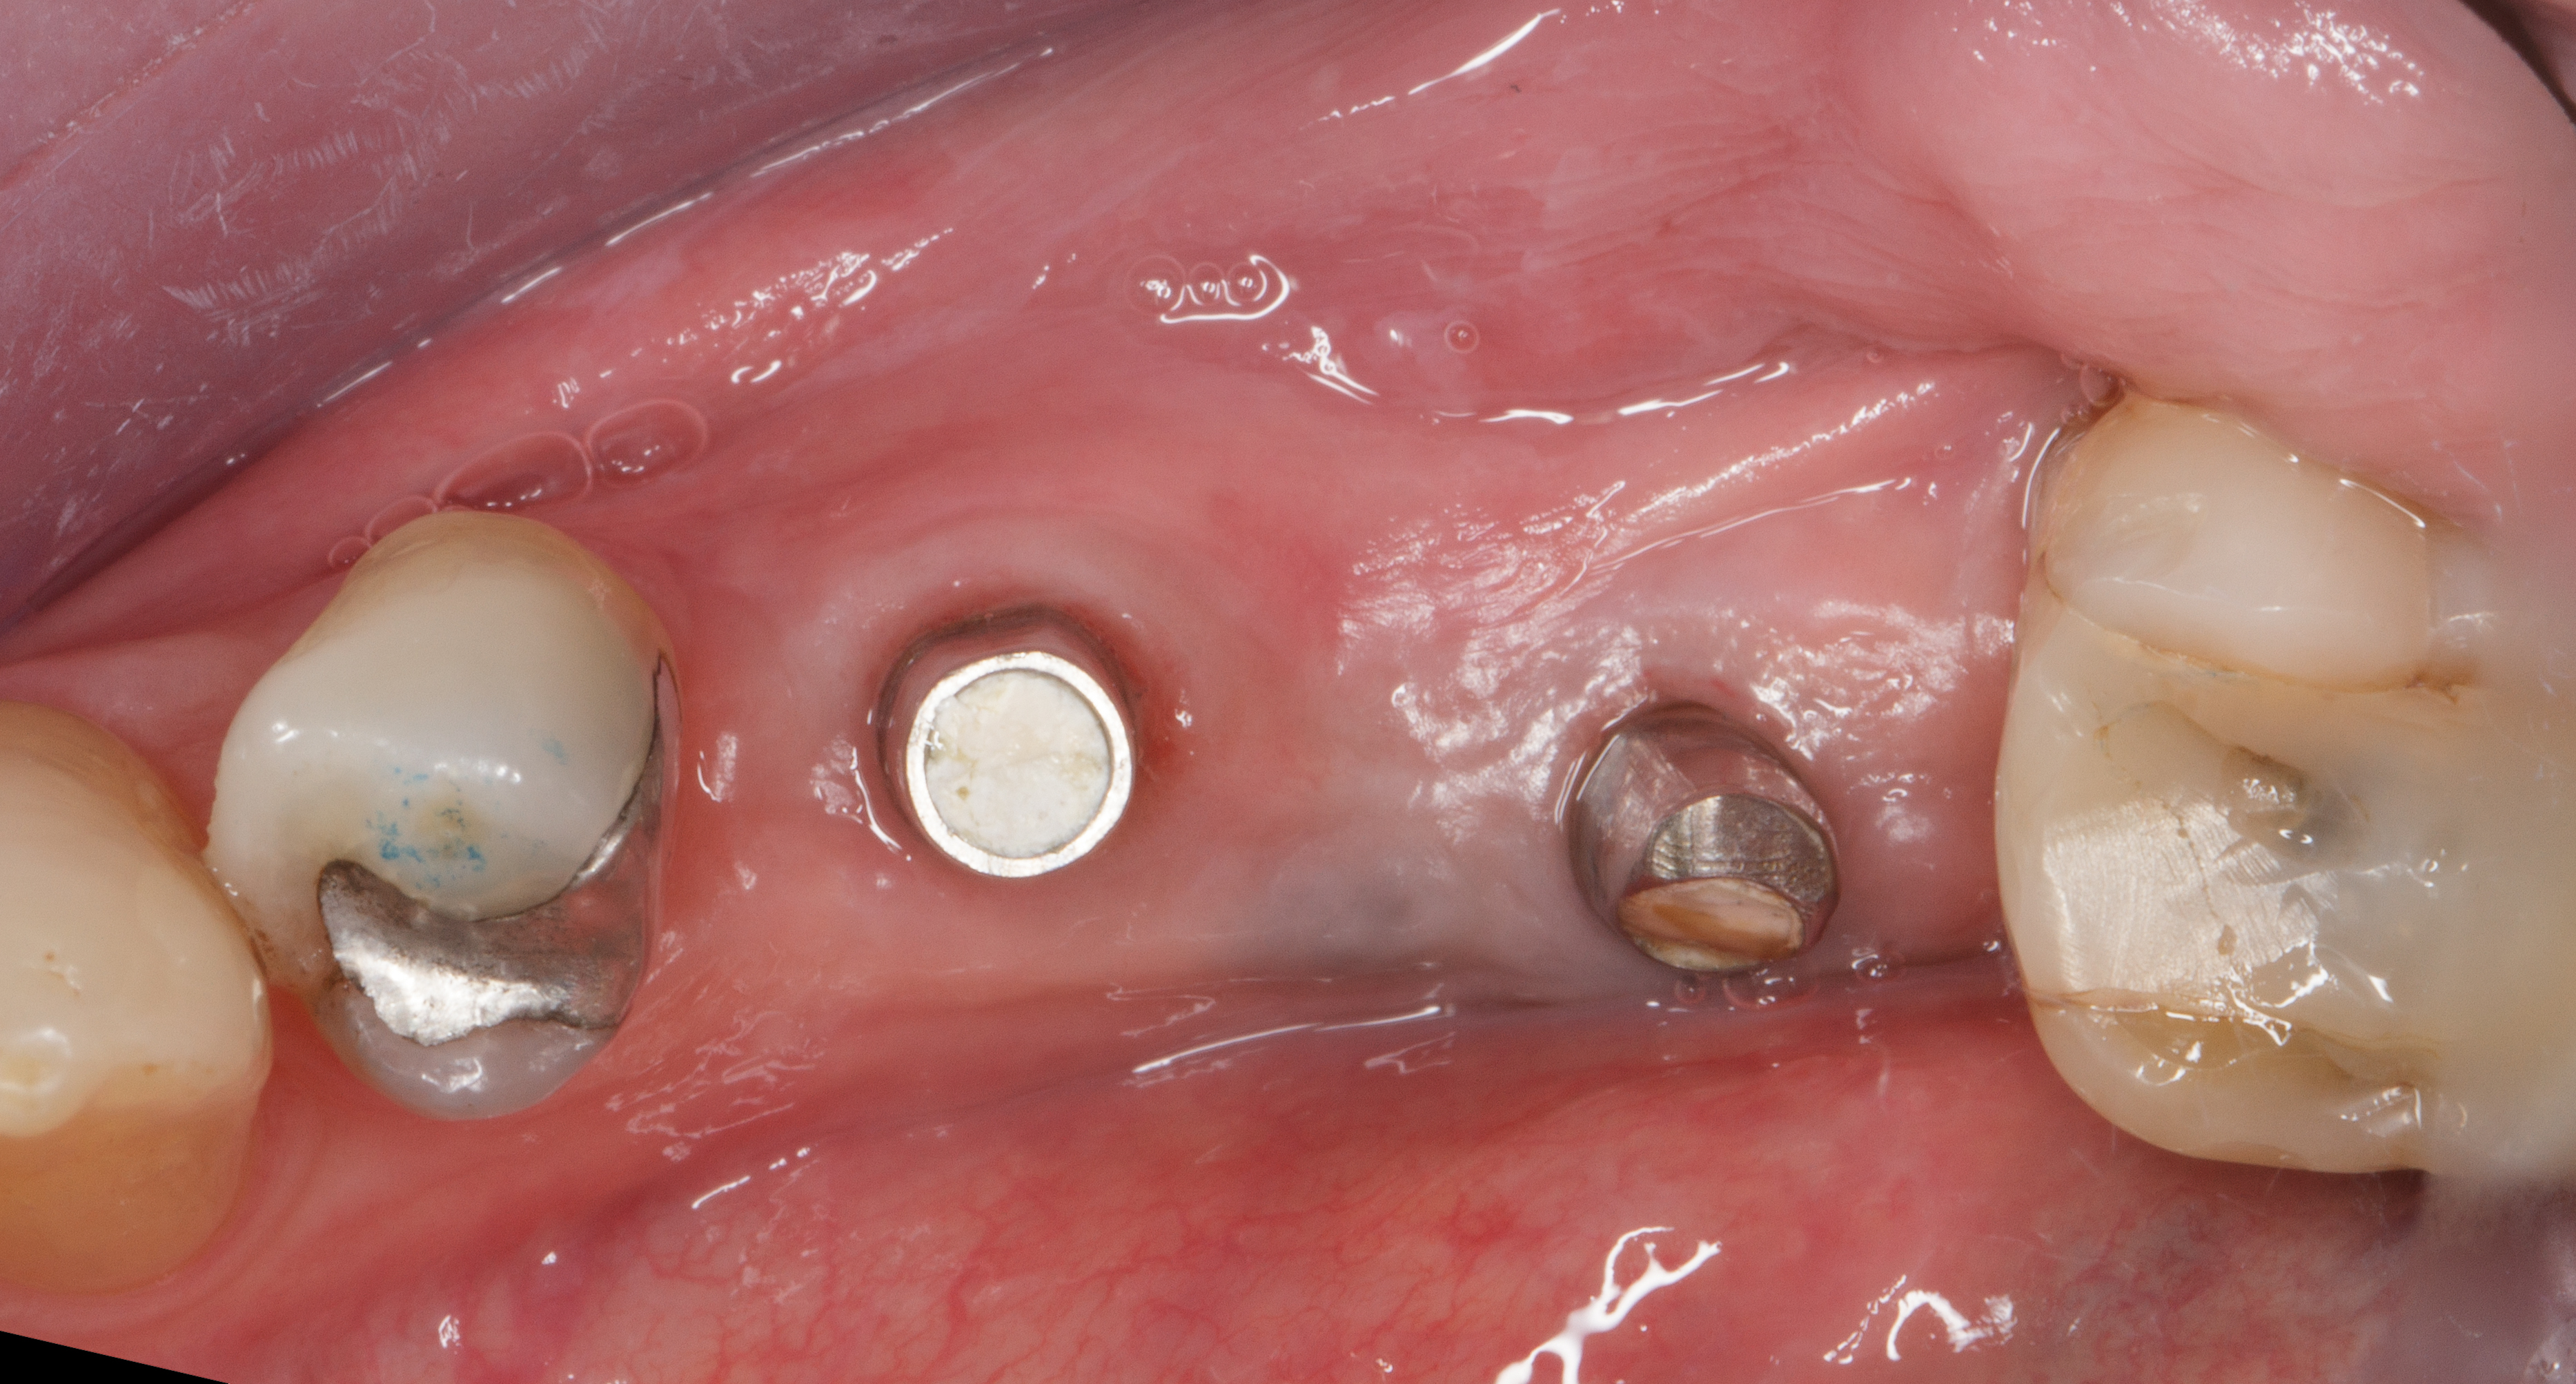

Dopo sei mesi dall’intervento di preservazione alveolare si inserisce un impianto differito in posizione 4.5.

Dopo esecuzione di lembo mucoperiosteo con una incisione di prolungamento mesiale a preservazione papillare, si osserva la presenza di tessuto osseo compatto in posizione premolare.

La corticale vestibolare e crestale non è ancora completamente formata, ma la visione in senso occlusale mostra come il tessuto osseo, che è ancora in fase di mineralizzazione, sia oltre il limite del bone housing dell’alveolo originario.

Si è ottenuta una preservazione del volume osseo oltre il 100% (Figure 18-19).